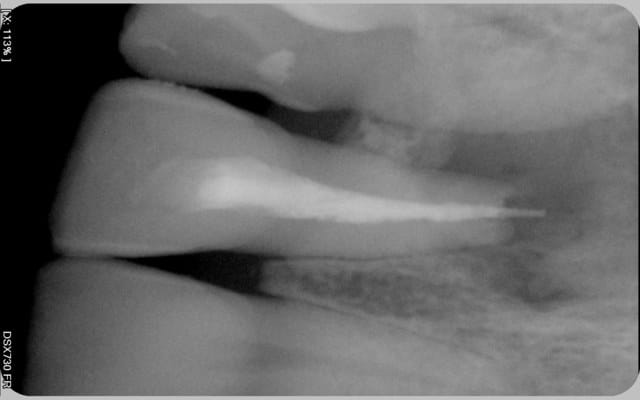

Ce matin, tout se passe bien, radio cône en place ok, mais pour la radio de contrôle finale je note un dépassement de 2mm.

Voici les photos.

Comme vous pouvez le voir la lésion est très importante. Pensez-vous que cette dent ai une chance? Mon maître de stage lui laissait 40% de chance, je n'ai pas de recul mais ça me semble beaucoup. J'ai preferé dire au patient que ça serrait délicat car il n'imaginait même pas la possibilité d'enlever la dent.

C ne en place ug4pvg - Eugenol

Obturation ocz3kw - Eugenol

Si je puis me permettre, pour le problème du dépassement, il faut que tu revois l'étape "ajustage du maître cône" pour faire tes endos.

Car je dirais, sur la radio d'essayage du cône, qu'il est ok en longueur, mais certainement pas en diamètre. Du coup, je pense qu'il frottait assez haut dans le canal et pas au niveau apical. Lorsque tu as condensé (j'imagine avec un spreader.), le cône a glissé à travers l'orifice apical.

Le secret est dans le "tug back".

D'accord avec Hinanui en ce qui concerne le maître cône et la nécessité d'une restistance au retrait, surtout quand l'apex paraît élargi comme c'est le cas sur ta radio.